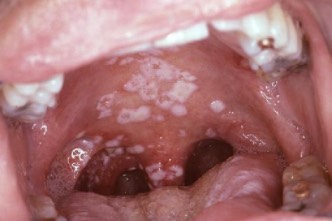

Chlamydia

Silent killer